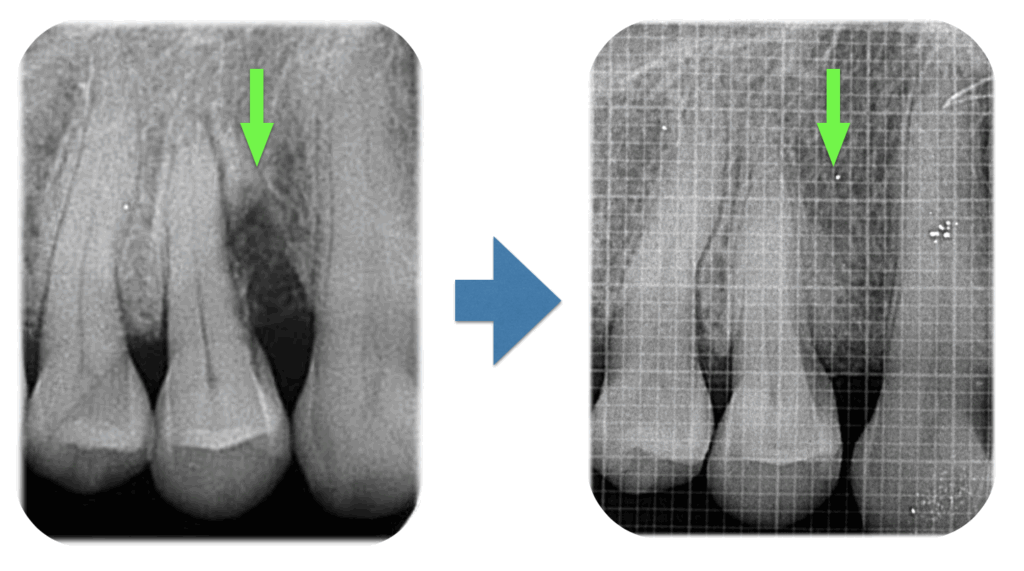

こんにちは。 暑い日が続いておりますが、体調など崩されていませんか? 熱中症など、皆様お気をつけてお過ごしください。 本日は、歯周組織再生療法をおこなった症例を紹介させていただきます。 左のレントゲ